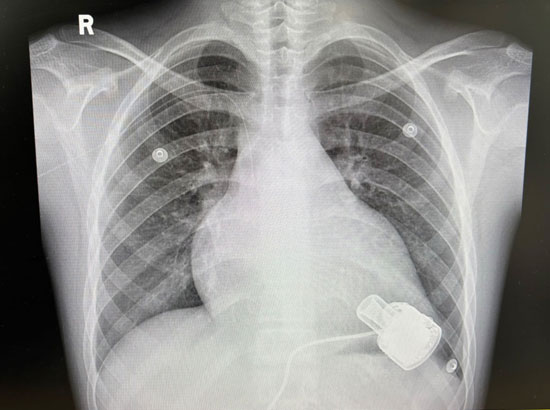

•     乐乐胸部的X片,右下角的机器就是人工心脏。

如果把听诊器放在乐乐(为保护未成年人,患者为化名——记者注)心脏的位置,听到的声音已不是“扑通、扑通”的心跳声,而是机器运转的嗡嗡声。是的,现在主要维持乐乐全身血液循环的,是一台机器,而不是心脏。这台机器大约有90克重,位于乐乐心脏的左心室。这颗人工心脏可以把充满氧气的血液泵向乐乐全身,让他像个健康人一样生活。

儿童常见的心衰发生在右心室,而乐乐的心衰发生在左心室。因此,人工心脏按在了乐乐的左心室。所谓的人工心脏其实是一个泵,泵的流入管对准左心室的二尖瓣膜,富含氧气的血液从肺部流经二尖瓣后,便会被机器抽入流入管,再通过机器泵进主动脉中。

人工心脏有两根电线连着两块电池,这两块电池在体外,所以现在乐乐的肚子上“长出了”两根电线,而且需要全天24小时携带着电池。除了两块供电电池外,还有4块备用电池。